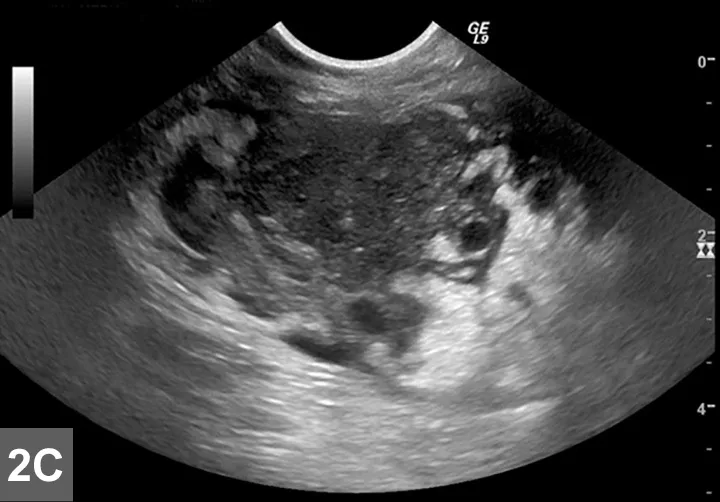

Featured Image

FIGURE 2B

Cranial mediastinal mass in a cat. There is also widening of the cranial mediastinum with rounded margins and border effacement of the cranial margin of the heart in the VD view. Pleural effusion contributes to effacement of the cardiac silhouette and to the widened appearance of the cranial mediastinum in the VD view (arrow).

Mediastinal

• Typically localized form of LSA involves infiltration of the thymus and/or cranial mediastinal and sternal lymph nodes with intermediate to large neoplastic lymphocytes with signs related to the intrathoracic mass effect and secondary pleural effusion (Figure 2).

• Thoracic radiographs may reveal a mediastinal mass effect.1-4

• Ultrasound can be used to visualize the cranial mediastinum and may reveal a hypoechoic mass or cluster of enlarged lymph nodes (Figure 5, see gallery).